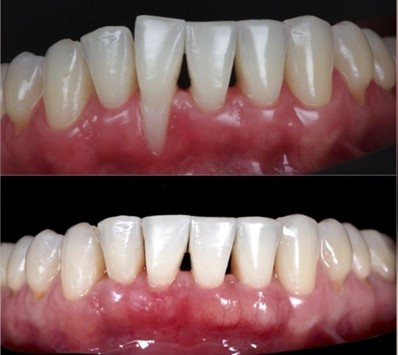

Можно сравнить эстетику до и после

Хирургические методы лечения рецессии десны существуют очень разные, и подбирать их нужно исходя из показаний. Иногда методы комбинируются.